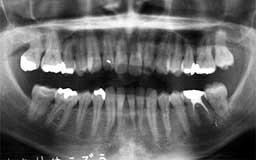

★ Uさん 38歳

当時の時代背景ということもあって、初診時38歳だったUさんのケースは少し特殊です。

メインテナンスは程度に応じて3か月・6か月・1年毎を選択するのが望ましいという保険上の

指導があったことも影響しています。多少将来が危ぶまれるものの、今すぐに何かが起こる

可能性は少ないという判断をしたUさんには3か月毎のメインテナンスを指示しました。

| Uさん 初診時 38歳 男性 歯槽骨破壊はそれほど著明ではないが、同じ年代のひとと比べれば歯槽膿漏の進行が少し 強そうな感じでした |

Uさん 20年後 57歳 長年にわたり変化のない推移だったがここ数年で急激な骨破壊を観察 |

話は戻りますが、そんななかでUさんは、唯一20年間3か月毎のメインテナンスを継続され

た貴重な存在でした。危ないから毎月に変更してもらおうと思いつつ、確実に3か月毎の予約

を守るUさんの診療態度とそれでも大きな変化もなく十分現状維持が保てている実績があって

そのままになっていました。ここ最近、左右の下顎臼歯部に急激な骨欠損が確認されたことか

ら、1か月毎のメインテナンスに切り替えることにしました。